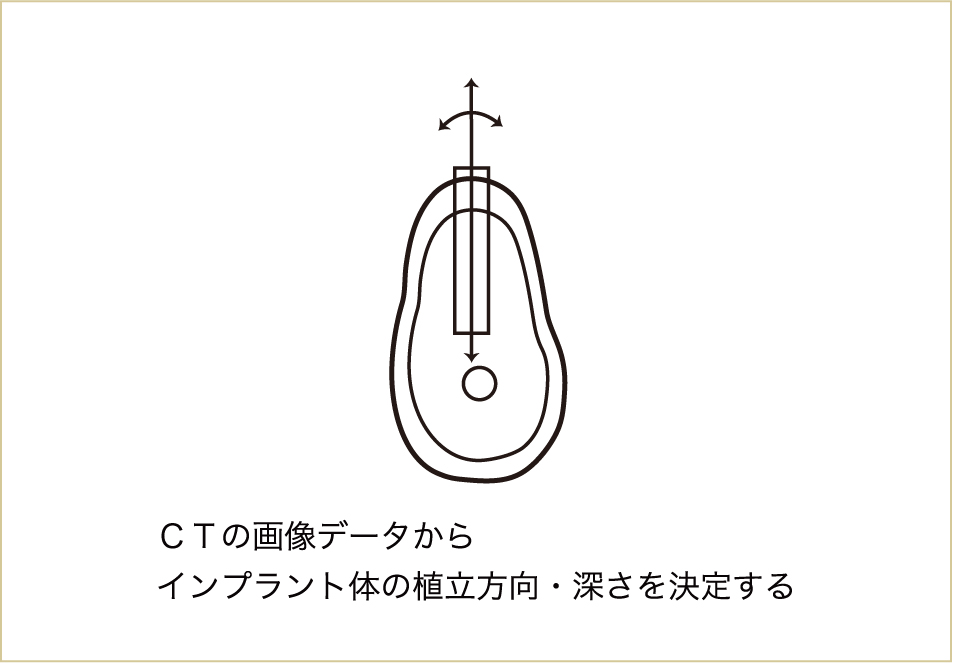

CTで、インプラント自体の方向、傾き、深さを立体的に決めることができるようになった。

CTによって、かなり高い精度で骨の構造が立体的に把握できるようになりました。最近では、このCTのデータをパソコン上でコンピューターガイドシステムとして手術のシミュレーション計画を立て、実際の外科手術を行う際に、反映させることもできるようになってきています。

CT上でインプラントを立てる位置、方向、長さ、深さなどを決定して、それを誘導するマウスピースのようなもの(サージカルテンプレートという)をつくり、それをガイドとして実際の手術を行います。

NobelGuide、iCAT、10DRなどと呼ばれているのが、このコンピューターガイドシステムです。

これまで術者の感覚のみで行っていた手術に比べ、CTの画像データを用いて診査することで、様々な偶発症を予防し、治療効果を上げることもできるようになり、安全性がより高まったといえます。